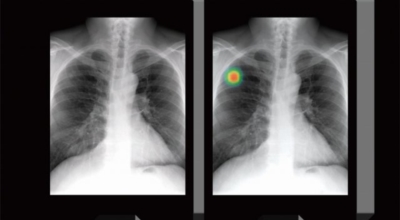

폐암 검사는 X-ray를 통해서 검사하는데 , 크기가 작거나 구석에 위치한 경우 확인이 어려운 경우도 있습니다. 그리고 조직 검사를 통해서 정확한 진단을 하게 돼요. 폐암이 발견되면 종양의 크기나 전이 여부 , 위치에 따라서 수술 여부를 결정하게 되어요.